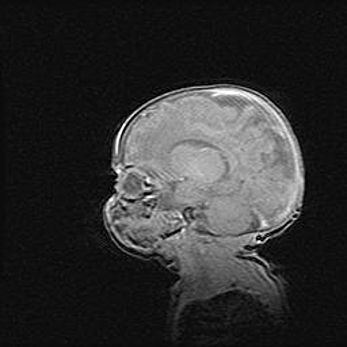

Наружная гидроцефалия с возможной атрофией височных областей.

Возраст: 28 дней

Вес: 3670 г

Пол: мужской

Окружность головы: 38 см

Срок гестации: 40 недель

Гидроцефалия головного мозга у новорожденных – это заболевание, которое характеризуется скоплением избыточного количества спинномозговой жидкости в желудочковой системе головного мозга в результате затруднения её перемещения от места выработки к месту поглощения в кровеносную систему или вследствие нарушения абсорбции. При открытой наружной форме гидроцефалии у новорожденных расширяются и переполняются субарахноидные пространства.

При нормотензивных  формах,  которые,  как  правило,  являются  следствием  перенесенных ишемических  повреждений  паренхимы  мозга,  возможно  сочетание микроцефалии  с нормотензивной гидроцефалией. В основе данных изменений лежит атрофия больших полушарий с преимущественной  локализацией  в  лобно-височных  областях.